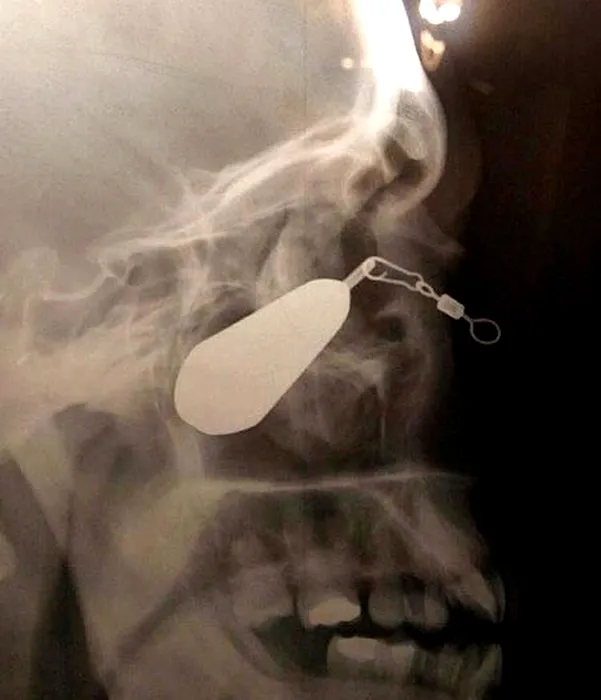

GALERIE FOTO: Cele mai terifiante radiografii